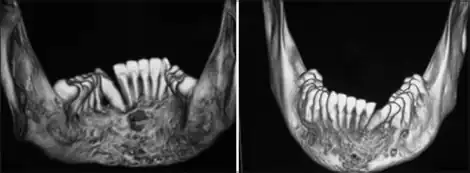

- Periodontitis, local inflammatory bone loss that can result in tooth loss.[16]